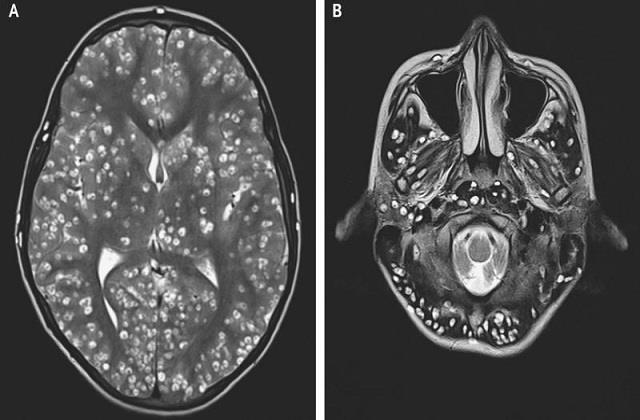

एमआरआई और सीटी स्कैन से पहचान

डॉक्टर इस बीमारी का पता एमआरआई (MRI) और सीटी स्कैन (CT Scan) से लगाते हैं। इससे सिस्ट का स्टेज पता चलता है

Vesicular Stage – शुरुआती अवस्था, सूजन नहीं होती।

Colloidal Stage – सिस्ट के आसपास सूजन और इंफ्लेमेशन।

Calcified Stage – पुराने सिस्ट कठोर होकर कैल्शियम जमने लगते हैं। जल्दी पहचान होने पर इलाज आसान और असरदार होता है।